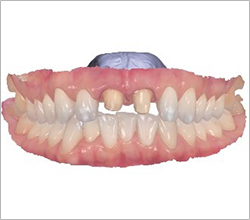

Full-mouth implants are highly advanced treatment

that require precise upper and lower occlusal harmony.

Patients themselves have proven us to be

a clinic specialized in full-mouth implant surgery.

Full-mouth implants are among the more complex dental procedures. They require careful decision-making, precise diagnosis based on each individual condition, and ongoing postoperative care after placement. With extensive experience in full-mouth implant treatment, Seoul The Nature Dental Clinic can provide systematic planning, placement, and follow-up care. Many patients continue to visit us through recommendations as a trusted clinic for full-mouth implants.

Dentures VS Full-Mouth Implants